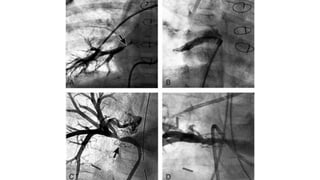

CARDIAC CATHERISATION

• Always Diagnostic

• Indication

✦ Measure PVRI / Reversibility in older children

✦ Diagnosis not clear on Echocardiography

✦ Intervention - BAS, PV dilatation, Vertical Vein Dilatation

• PA/PV Angiogram

✦ PA injection with venous follow through preferred over direct PV injection

✦ Anatomy of TAPVC

✦ Type

✦ Drainage

✦ Site of Obstruction

• Oximetry

✦ Similar saturation in all chamber

• Drawbacks

✦ Delays management

✦ Aggravate pulmonary edema

✦ Contrast related

SC-TAPVC CATHETER ANGIO

IC-TAPVC CATHTER ANGIO